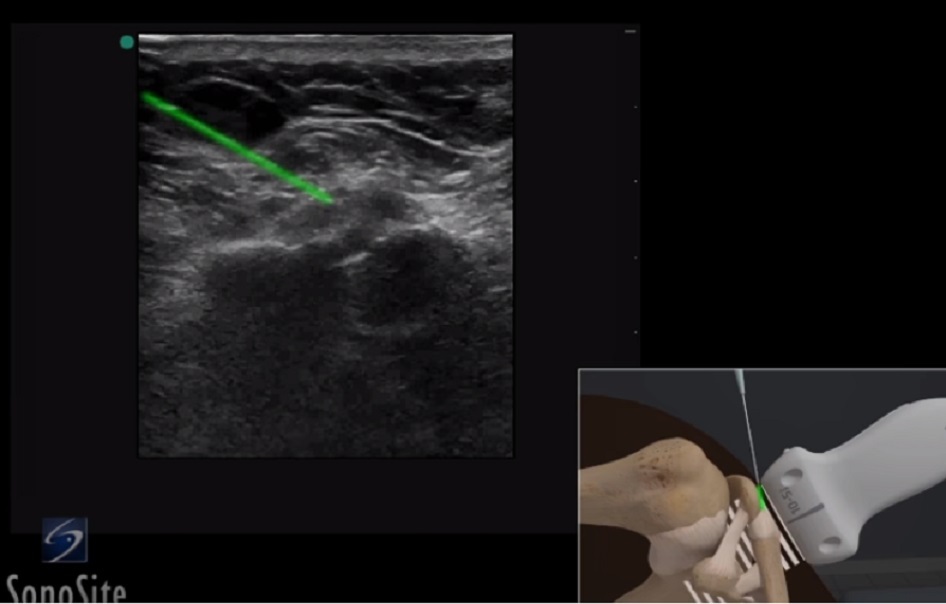

肩鎖関節針画像